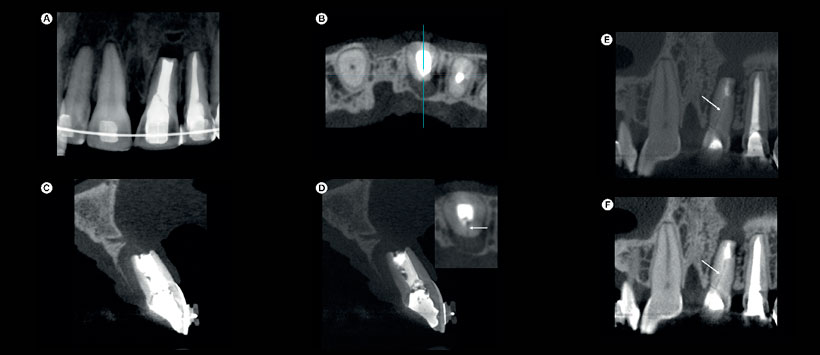

Figura 1: (A-B) El informe de CBCT producido por e-Vol DX muestra los dientes # 11 y 21 con artefactos de contraste blancos, lo que dificulta la identificación del tratamiento fallido del conducto radicular; (C-H) en las imágenes de e-Vol DX CBCT, se usó el filtro y se conservó el contraste de la escala de grises, lo que reduce las áreas blancas de la imagen original.

Figura 2: (A-B) las imágenes de e-Vol DX CBCT que muestran el diente n. ° 21 con artefactos de contraste blanco evitan la visualización de una fractura de raíz vertical y ocultan una rarefacción lateral; (C-F) En las imágenes CBCT producidas con un filtro para el contraste normal de la escala de grises, se reducen las áreas claras y la fractura radicular vertical palatina se puede identificar más fácilmente. Figura 3: (A-B) Las imágenes de e-Vol DX CBCT revelan un canal lateral en el diente # 37; (C-F) El filtro favorece la visualización de los detalles anatómicos de este canal lateral interno y su superficie externa (ligamento periodontal) se puede ver claramente a mayores aumentos.